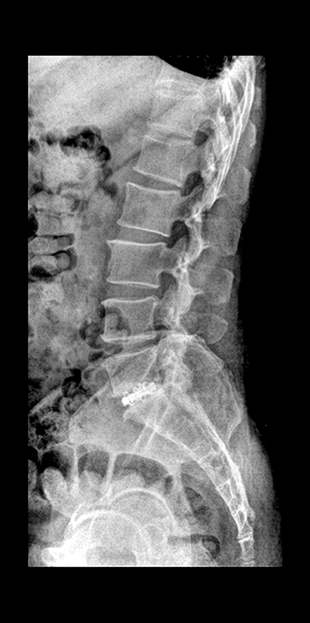

윤성훈 과장신경외과

요통, 경추통, 방사통, 척추 골절, 척추 디스크, 척추관협착증, 척추전방전위증, 신경차단술, 척추신경성형술, 디스크고주파 감압술, 양방향 / 단일공 내시경하 수핵제거술, 척추 풍선복원술, 경추/요추 퇴행성질환 교정술 등